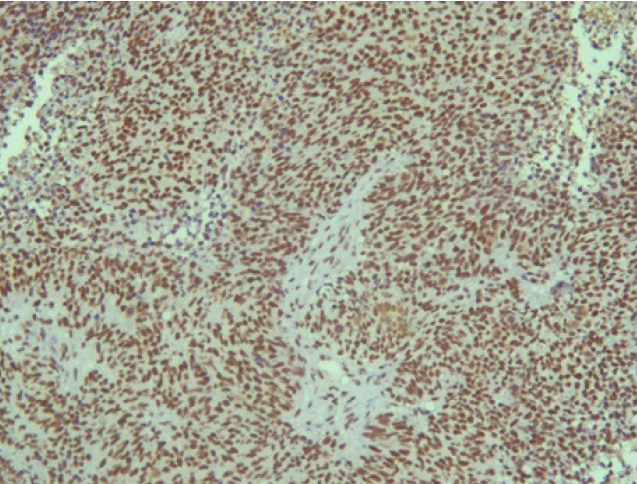

Поэтому при первичном гистологическом исследовании диагноз эстезионейробластомы был установлен только у 6 пациентов (66,6 %), у троих больных (33,4 %) были диагностированы другие формы злокачественного процесса, что не соответствовало клиническим проявлениям. Во всех случаях проводили иммуногистохимическое (ИГХ) исследование. ИГХ-исследование проводили на срезах с парафиновых блоков с использованием антител к Keratin.Pan (AE/AE3), CD45 (Cocktail), Synaptophysin (SP11), ChromograninA (SP12), CD56 (56C04), Ki-67 (30-9), p63 (7JUL)RTU, S100, INI1, CD99 (HO36-1.1). Также выполняли доставку с антителами к EMA (E29), TTF1 (8G7G3/1). В диагностических материалах была отмечена положительная экспрессия Synaptophysin, ChromograninA, CD56, Ki-67 (до 90% ядер), INI1 (рис. 2–6).

Рис. 2. Synaptophysin [SP 11] ×200

Рис. 3. Chromagranin A [SP 12] ×200

Рис. 4. CD 56 [56C04] ×200

Рис. 5. Ki-67 [30-9] (90%) ×200

Рис. 6. INI 1 ×200

Эти результаты иммуногистохимического исследования подтверждают наибольшее соответствие иммунофенотипа опухоли – ольфакторной нейробластоме (G3 по Hyams) М9522/33.